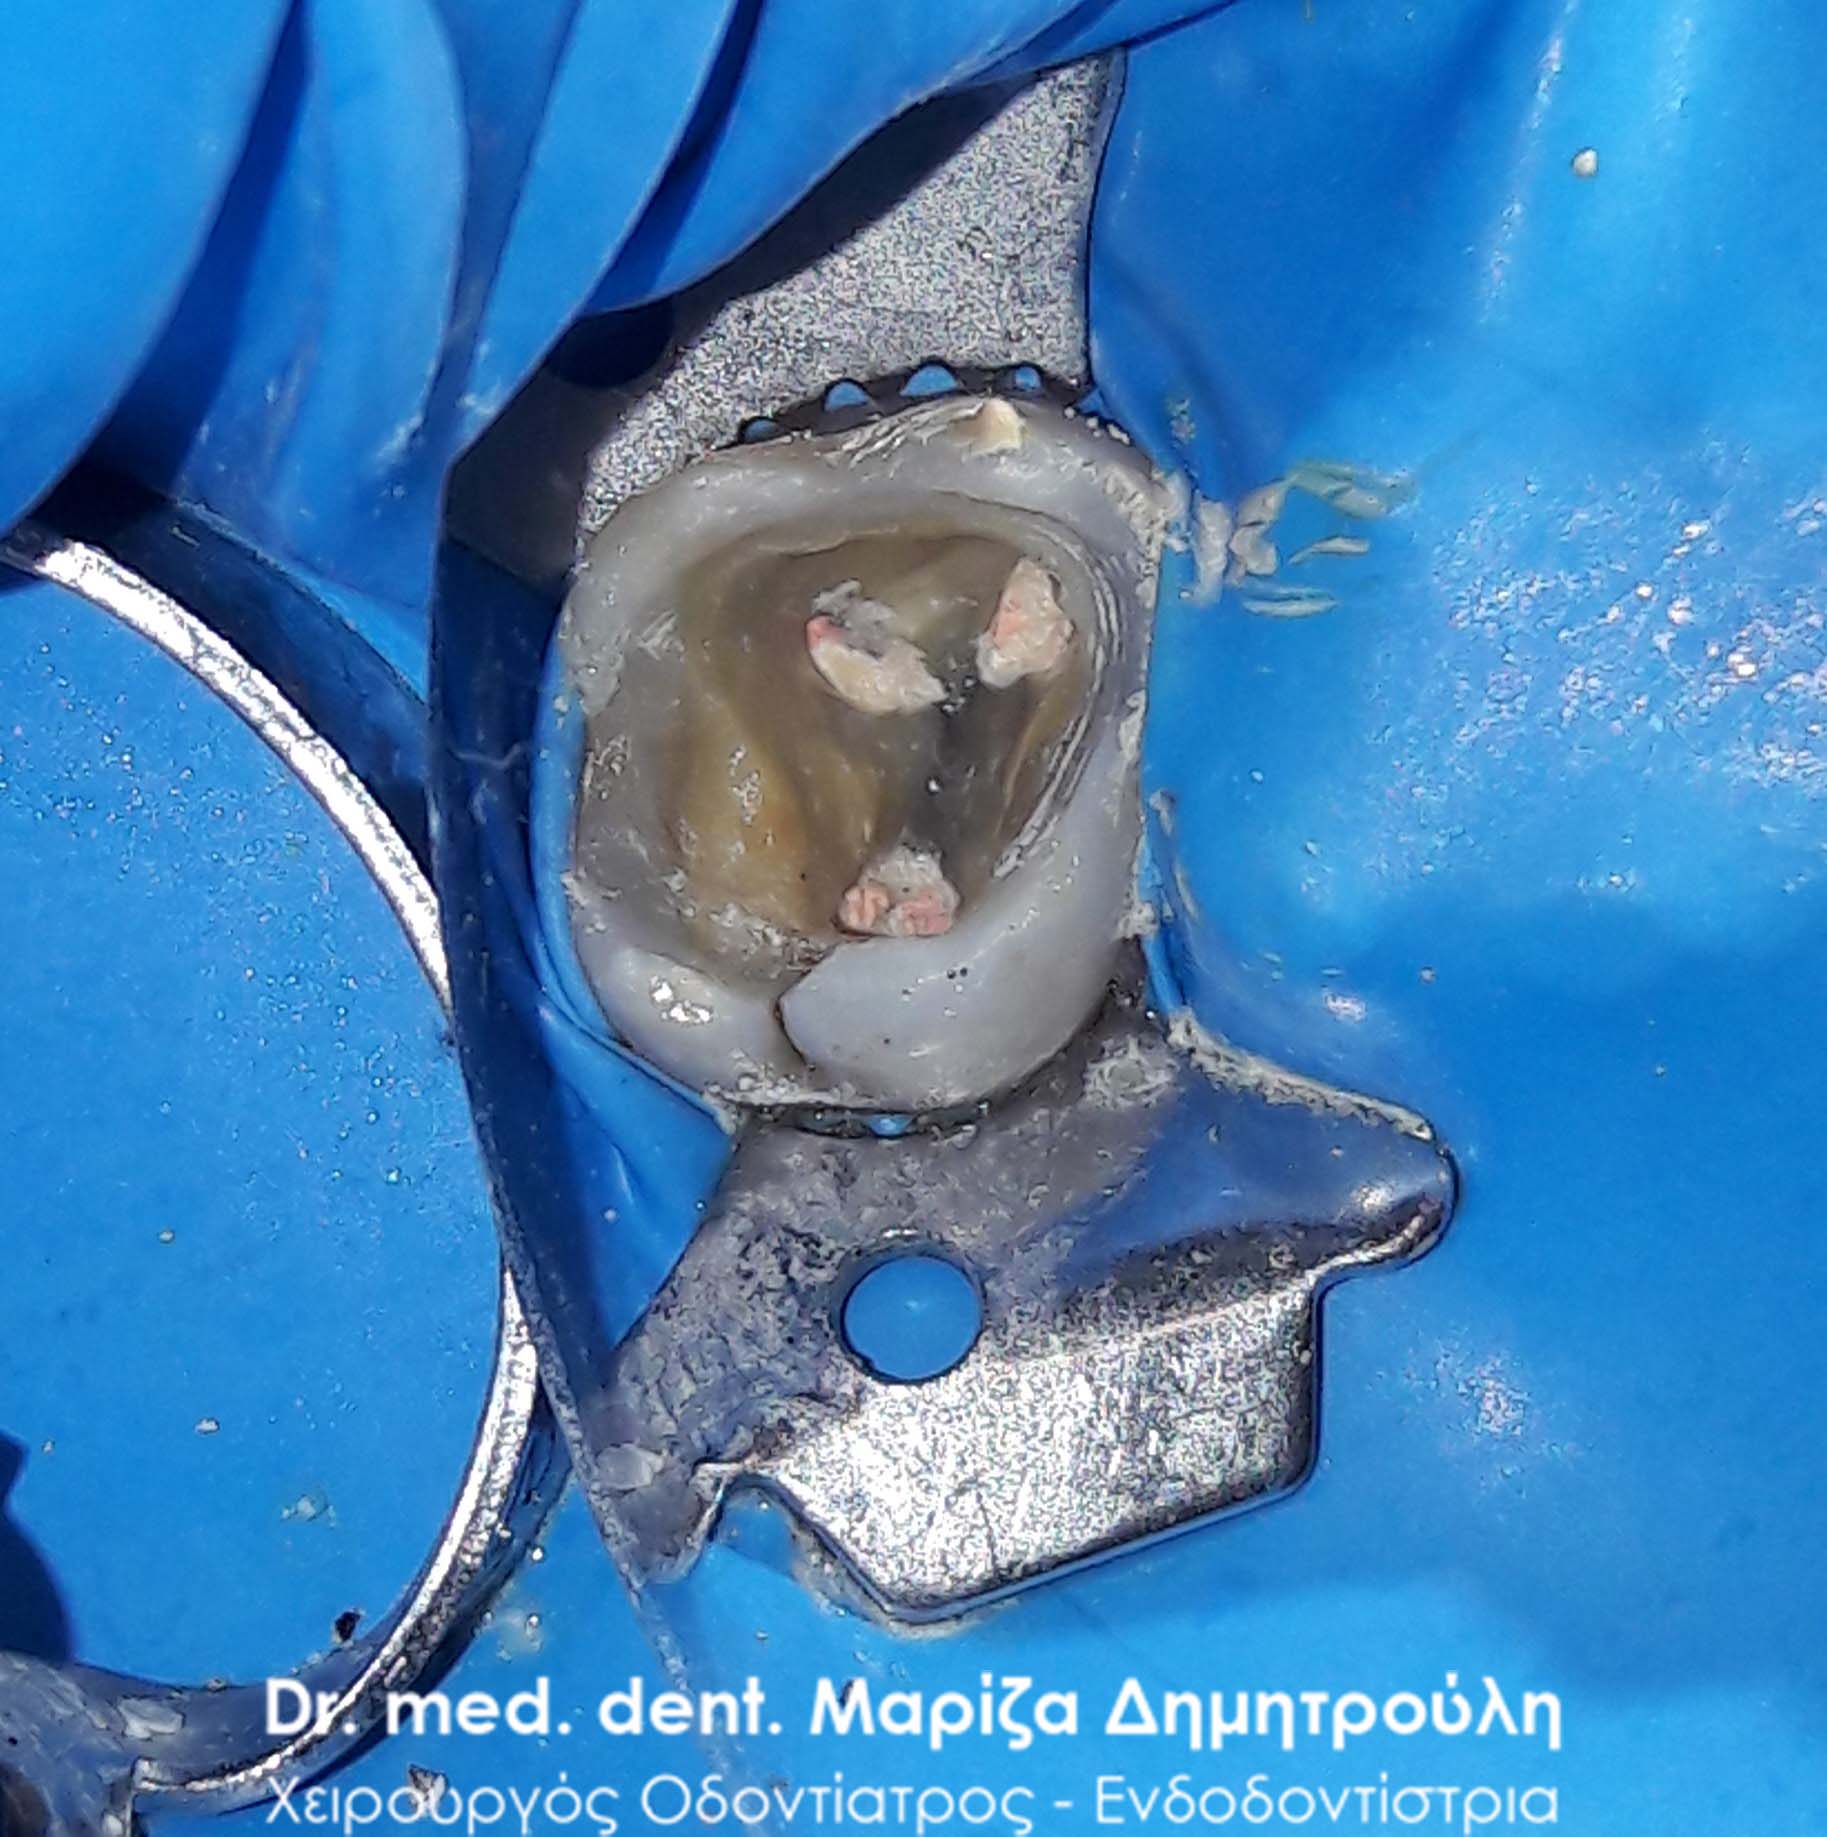

Pus after opening the tooth